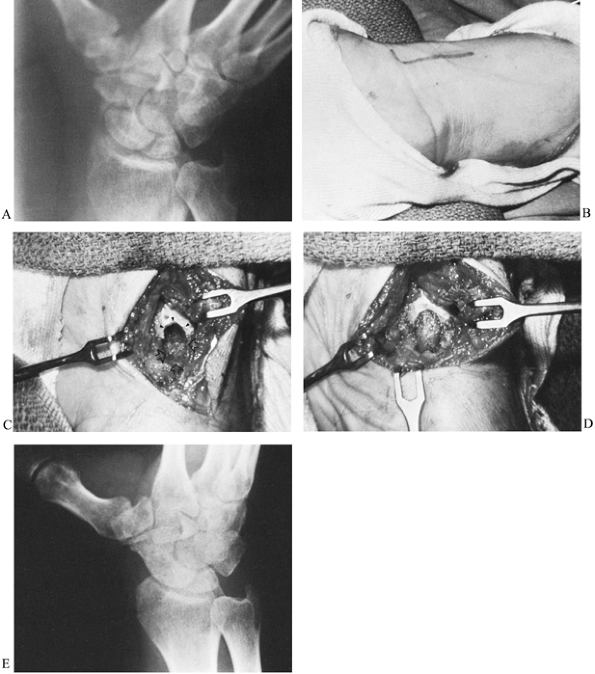

Figure 42.9. A:

Radiograph of a scaphoid nonunion in a 38-year-old accountant. The likelihood of achieving healing is minimal with a bone graft when there is a small proximal fracture fragment whose sclerotic appearance indicates avascular necrosis. B: The proximal fragment was excised, and a coiled piece of palmaris longus tendon (arrows) was inserted into the void. C: A radiograph 2 years later showed no secondary shifting of any carpal bone. D,E: The patient regained satisfactory pain-free wrist mobility. |